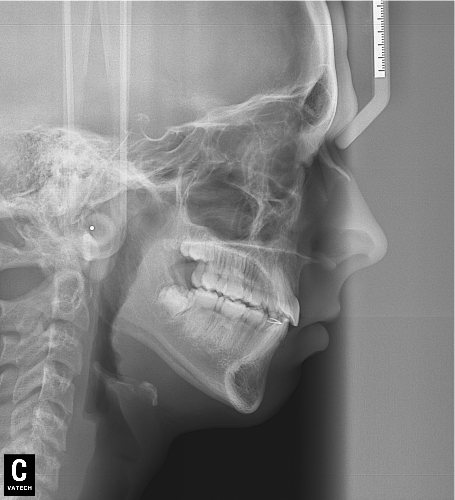

El paciente D.M. llega a nuestra consulta sin los 2 premolares inferiores que le quitaron en anteriormente para empezar a mejorar el caso.

– Perfil plano

– Clase III esquelética

– Clase III dental

– Apiñamiento superior muy importante